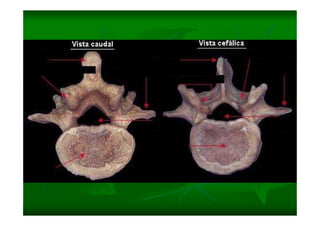

Este documento describe la columna vertebral humana. Está compuesta de 33 vértebras divididas en 7 cervicales, 12 torácicas, 5 lumbares, 5 sacras y 4 cóccigeas. Cada vértebra posee un cuerpo, pedículo, apófisis transversas, apófisis espinosa e inferior y laminas. Las curvaturas de la columna son la lordosis cervical y lumbar y la cifosis torácica y sacra.